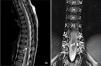

Resonancia magnética de la columna vertebral que revela una malformación arteriovenosa intramedular a nivel de D10 (flecha), caracterizada por ectasia y hematomielia. La hematomielia aparecía con hipointensidad en imágenes ponderadas en T2, extendiéndose a través del conducto ependimario en sentido cefálico hasta D9 y en sentido caudal hasta el cono medular. A la vez, se observó hiperintensidad intramedular extensa hasta C2, atribuida a congestión venosa (triángulo), así como dilatación de las venas perimedulares posteriores (rombo).